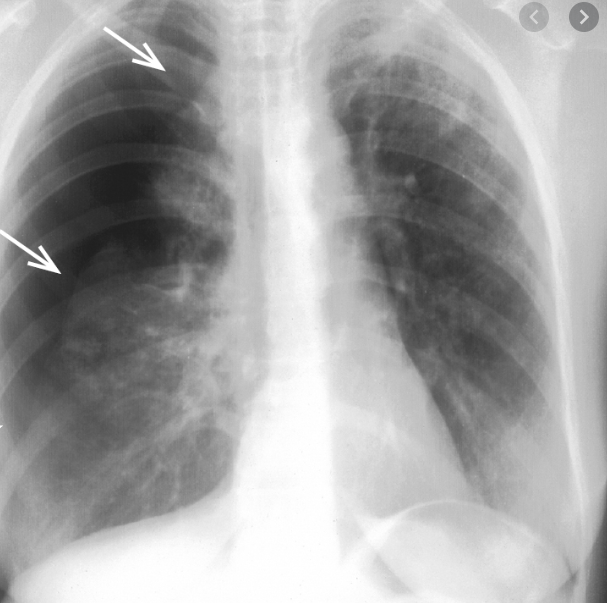

Diagnosing Pneumothorax: Medical Approaches

Accurate diagnosis of pneumothorax is essential for appropriate treatment. Healthcare providers use various methods to confirm the presence and extent of a collapsed lung.

Diagnostic Tools for Pneumothorax

- Chest X-ray

- CT scan

- Ultrasound

- Physical examination

A chest X-ray is typically the first-line diagnostic tool, providing a clear image of the lungs and any air in the pleural space. CT scans offer more detailed images and can detect smaller pneumothoraces that might be missed on X-rays.

Your doctor will probably start with a physical exam. They’ll listen to your breathing through a stethoscope and tap your chest to find out if it sounds hollow.

You might have tests including:

- X-rays, so your doctor can see the outline of your lung

- A CT scan, a series of X-rays that a computer turns into a detailed image of your lung